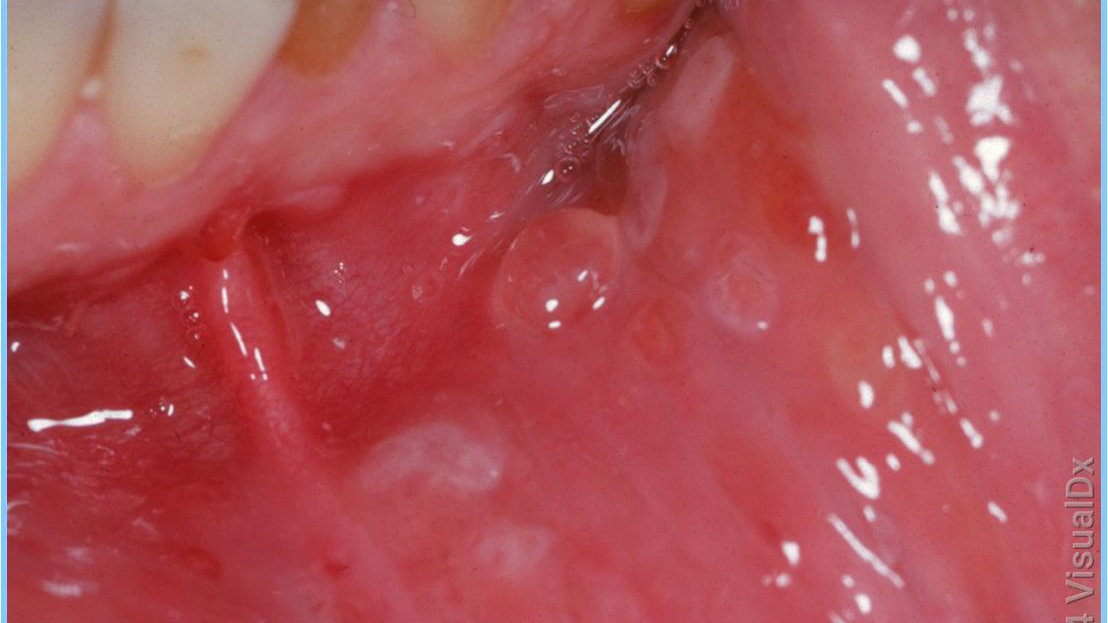

Hastalığın belirtilerinden bahseden Doğancı, “Tipik bulgular el ve ayaklarda, bazen yüzde yaygın kırmızı, mor renkte döküntü, ateş, ağız içinde ve damak ve boğaz mukozasında tipik lezyonlar nedeniyle şiddetli boğaz ağrısı şeklindedir” dedi. Şiddetli ağrının çocukların beslenmesini olumsuz etkileyebileceğini belirten Doğancı, “Ağrı nedeniyle küçük çocukların beslenmesi bozularak sıvı ve beslenme yetersizliği oluşturabilir. Parmaklardaki döküntüler de şiddetli ağrıya yol açabilir. En belirgin sorun, ağız içi lezyonlarından kaynaklanan şiddetli ağrı ve yutma güçlüğüdür” şeklinde konuştu. Özellikle çok küçük çocukların beslenmeyi ve hatta su içmeyi reddedebileceğini vurgulayan Doğancı, bunun sonucunda dehidrasyon yani susuz kalma riskinin ortaya çıkabileceğine dikkat çekti.